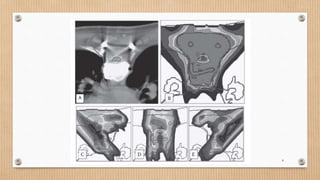

Dose distribution of

individual beams

(A) Conventional IMPT

(B) Robust IMPT - Range uncertainty only

(C) Robust IMPT - Setup uncertainty only

(D)Robust IMPT - Considering both range

and setup uncertainty

• 39.

Dose distribution of individualbeams (A) Conventional IMPT (B) Robust IMPT - Range uncertainty only (C) Robust IMPT - Setup uncertainty only (D)Robust IMPT - Considering both range and setup uncertainty 39